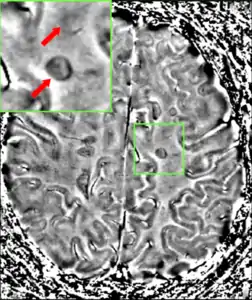

MRI brain scan produced using a Gradient-echo phase sequence showing an iron deposit in a white matter lesion (inside green box in the middle of the image; enhanced and marked by red arrow top-left corner)[213]

Improvement in neuroimaging techniques such as positron emission tomography (PET) or MRI carry a promise for better diagnosis and prognosis predictions. Regarding MRI, there are several techniques that have already shown some usefulness in research settings and could be introduced into clinical practice, such as double-inversion recovery sequences, magnetization transfer, diffusion tensor, and functional magnetic resonance imaging.[216] These techniques are more specific for the disease than existing ones, but still lack some standardization of acquisition protocols and the creation of normative values.[216] This is particularly the case for proton magnetic resonance spectroscopy, for which a number of methodological variations observed in the literature may underlie continued inconsistencies in central nervous system metabolic abnormalities, particularly in N-acetyl aspartate, myoinositol, choline, glutamate, GABA, and GSH, observed for multiple sclerosis and its subtypes.[217] There are other techniques under development that include contrast agents capable of measuring levels of peripheral macrophages, inflammation, or neuronal dysfunction,[216] and techniques that measure iron deposition that could serve to determine the role of this feature in MS, or that of cerebral perfusion.[216]